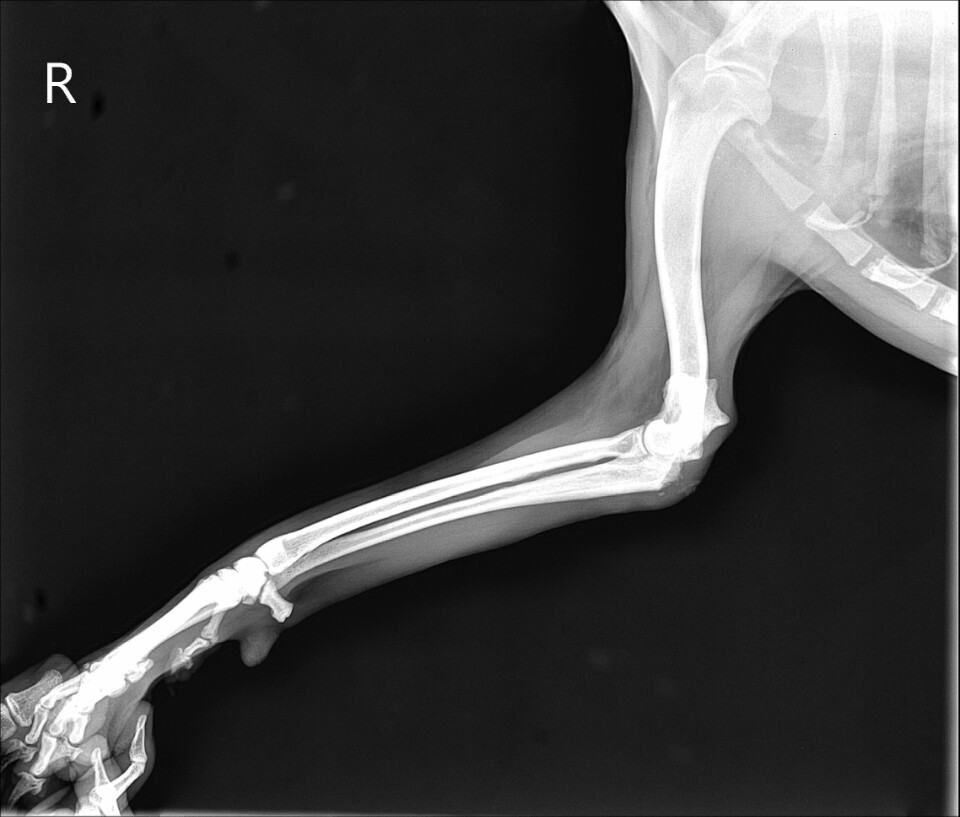

KakaoTalk_20201105_203249339.jpg

KakaoTalk_20201105_203238755.jpg 위의 사진은 왼쪽 팔의 사진이고 아래는 오른쪽 팔의 사진이다. 왼쪽 팔과 비교할때 오른쪽 팔꿈치의 골절이 보인다.

화복이를 병원에 데려가 사진을 찍어보자 팔꿈치 골절이었다. 수술이 필요한 상황이었지만 내가 다니는 병원은 정형외과 선생님이 파트로 계시는 병원이었다. 하필 그때가 추석이었고 정형 선생님이 나오시려면 한참 후에나 가능했다. 그래서 부득이하게 수술이 또 늦어지게 되었다. 골절은 시간이 지연될수록 골편을 제자리에 맞추기 힘들어 진다고 한다. 결국 수술을 하기 위해 정형 선생님이 풀타임으로 근무하시는 병원까지 내원하게 되었다. 왕복 4시간 거리의 병원이었다. 부모님과 함께 화복이를 태우고 병원으로 가서 다시 사진을 찍고 긴 상담을 했다. 결론은 수술을 해봐야 알수 있지만 성공률이 낮을 수밖에 없다는 것이었다. 나의 자책감은 하늘을 찔렀다. 어떻게 이렇게 멍청하게 대처를 할 수 있었을까? 아무리 되집어보아도 일말의 변명거리가 생각나지 않았다.